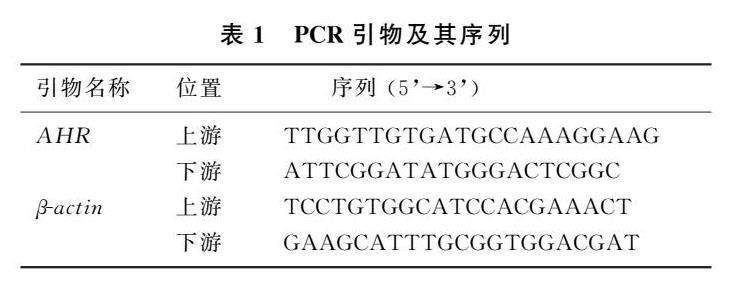

论著 | 芳香烃受体在EBV阳性鼻咽癌细胞系中生物学功能

论著 | 芳香烃受体在EBV阳性鼻咽癌细胞系中生物学功能